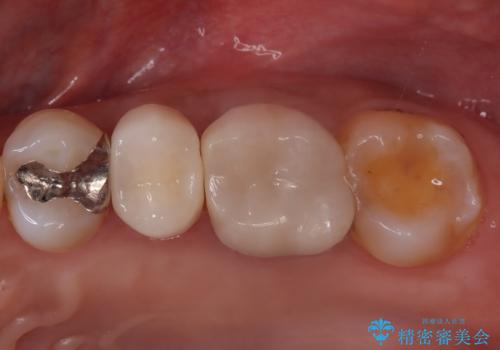

検査で見つかった虫歯 セラミッククラウンでの治療

担当医 岡田康成